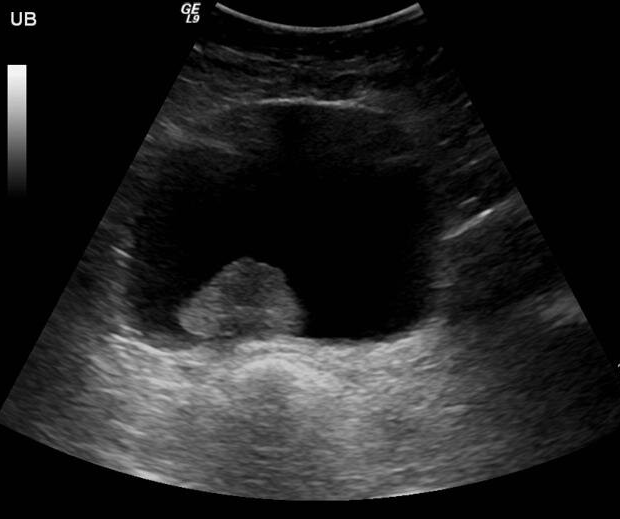

소변검사, 방광초음파, 방광내시경, 방광암표지자검사, 요세포검사